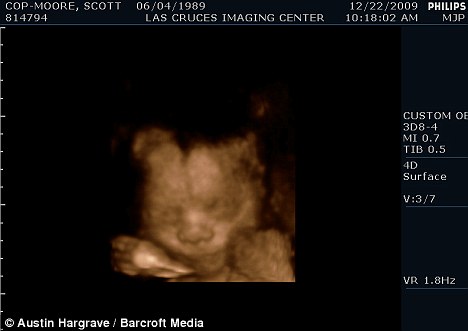

扫描显示斯科特怀的是个男孩

现年30岁的斯科特·穆尔和丈夫托马斯来自美国加利福尼亚州,两人原先都是女性,托马斯接受过变性手术后成为真正的男子汉,斯科特仍然留有一些女性器官并持有女性出生证明,所以他们的婚姻是合法的。目前他们已经知道未出生的孩子是个男孩,准备给他取名“迈尔斯”。

2009年6月,斯科特从一名男性朋友那里取得精子,并通过人工受精成功怀孕。他打算在当地的医院自然分娩。